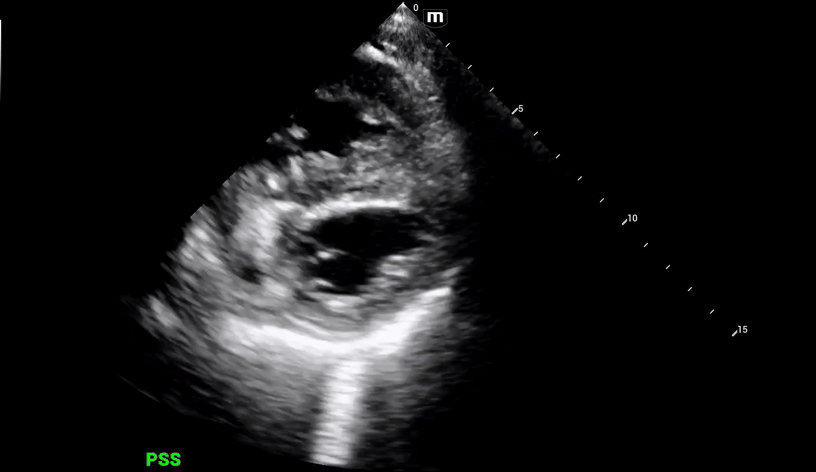

Additional views were obtained showing RV strain (likely chronic) in the PSS (below) as well as significantly enlarged RA and RV chambers, as noted in the A4C view (below).